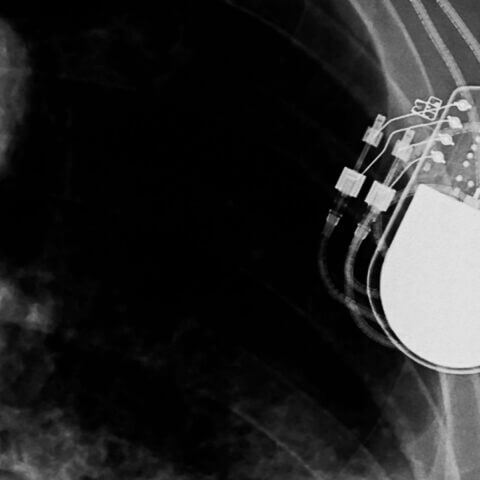

•  Different timelines — Depending on the purpose, medical devices may undergo dynamic changes in function and safety over years or even decades certainly when being implanted. Others may be of short-term usage to support a diagnosis or treatment delivery. In any case, clinical evidence will be needed to support safety, clinical performance and clinical benefit claims for medical devices to support market entry (PMAs, CE marking etc.) as well as keep already placed devices on the market (e.g. mandated PMCF studies in the EU).

• Post-approval studies continue after a device has been released to the public. They evaluate long-term safety and efficacy data. For devices such as permanent prosthetic implants, the findings of these studies are the most clinically useful but may take decades to gather.